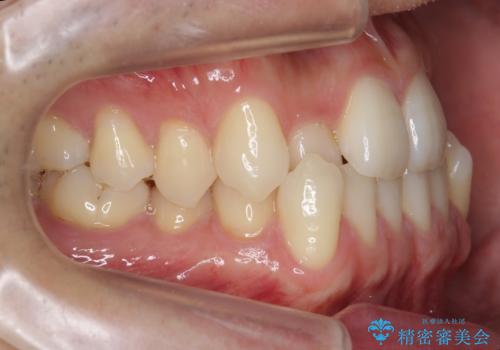

前歯の反対咬合でしたが、かみ合わせが、下顎が大きく前方にずれていました。

引っ込んでいる前歯の前方に下の犬歯が深く咬み込んでおり、また、奥歯のかみ合わせも受け口方向にずれ、骨格性の反対咬合も少々ありました。